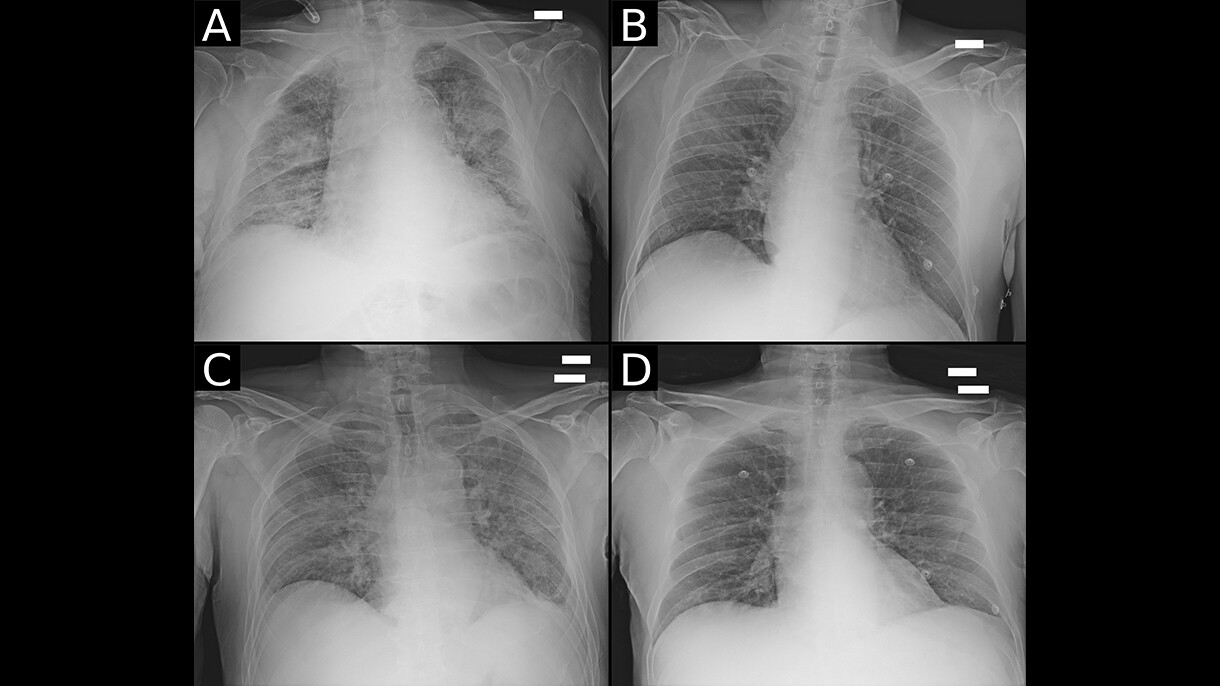

Centro Diagnostico Italiano and Bracco Imaging create open-source imaging archive project

A consortium of healthcare and research organizations led by Centro Diagnostico Italiano and Bracco Imaging collaborated to create the AIforCOVID Imaging Archive, a repository with almost 1,000 chest X-rays and anonymized clinical data of COVID-19 patients. Images and clinical data were analyzed using three machine learning approaches developed by the research organizations and performed on AWS. Based on these analyses, the consortium developed a model that is able to predict the clinical outcome of COVID-19 patients from chest X-ray images and clinical data. All data collected by the AIforCOVID network is available for download to members of the international scientific community from the project's website.

“Radiological imaging is playing a crucial role in COVID-19 patient management for diagnosis and treatment selection. Thanks to the power of machine learning delivered by AWS’s technology and professional support, we have been able to quickly make sense of the vast volume of data generated by diagnostic imaging and clinical analyses," said Sergio Papa, director of diagnostic imaging and stereotactic radiosurgery, Centro Diagnostico Italiano. "We are working to deliver a practical resource that hospitals and organizations around the world can apply to increase their understanding of the disease, facilitate their own diagnostic efforts, and improve patient treatment"